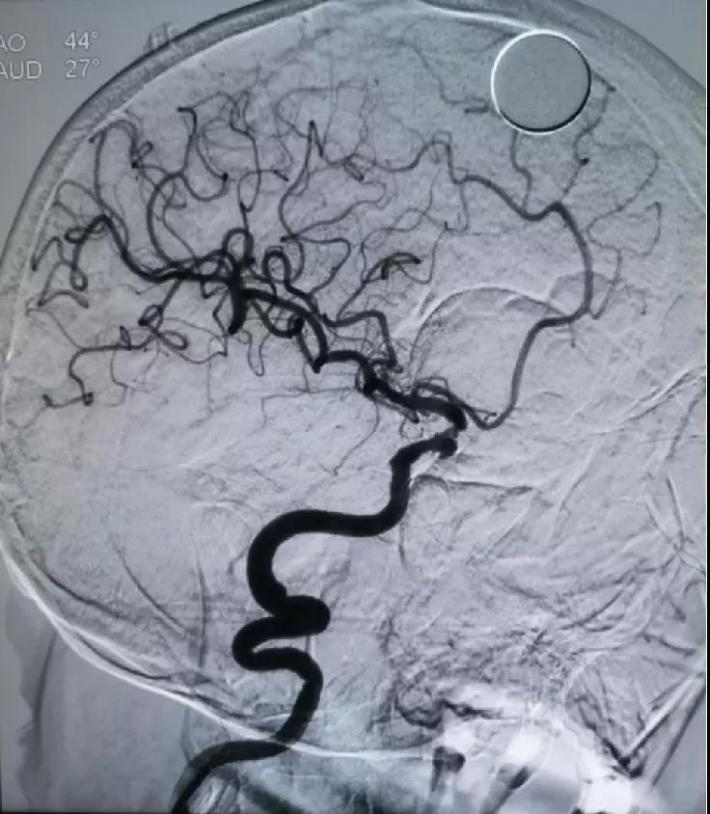

DSA

右侧颈内动脉虹吸段夹层动脉瘤,右侧大脑前动脉A1段纤细

预置入支架导管,栓塞动脉瘤用微导管头端超选进入动脉瘤腔,通过支架导管送入Enterprise支架(4.5*22mm)并打开支架,填入弹簧圈栓塞夹层动脉瘤。但此时发现大脑前动脉A1段不显影。

对侧造影评估,前交通开放,左侧大脑前动脉经开放良好的前交通动脉向右侧大脑前动脉A2段各分支血管供血良好,结束手术

✔Enterprise支架释放后,右侧大脑前动脉A1段未显影,考虑可能为支架打开后,对病变段血管的修复及一定血流导向作用,大脑中动脉前向血流增加,而原本纤细的左侧大脑前动脉A1段血流减少,对侧大脑前动脉通过前交通动脉向左侧大脑前动脉A2段主流供血,由于血流对冲作用至左侧大脑前动脉A1段不显影。后对侧评估前交通开放,对侧代偿良好,结束手术。术后患者亦未再出现新的神经系统体征,肢体活动及语言功能恢复良好,1周后头颅CT未见新发梗死灶。